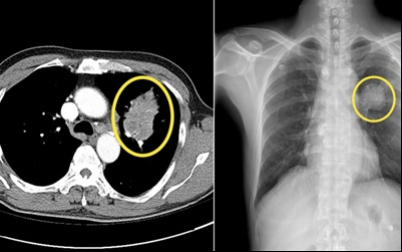

3. 폐암 초기 증상 - 잔기침

평소 보다 잔기침이 많아지면 위험하다고 합니다 . 폐에 문제가 생겼다는 신호 중 하나 라고 합니다 . 그리고 폐암은 초기 발견이 어렵다고 하므로 , 보다 세심한 관찰이 필요한 것 같습니다 .